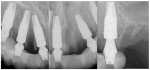

At the initial visit a panoramic x-ray (Figure 11) and periapical x-rays were taken. The patient was photographed to capture her full face and shoulders, and a digital scan (TRIOS 4) of the maxillary dentition was obtained. This file was electronically sent to the implant company (Osteon Medical) to complete the VSD.

A week later the patient presented for surgery for extraction and replacement of her existing maxillary dentition with implants and a screw-retained provisional implant restoration. Teeth Nos. 2, 4, 6 through 11, 13, and 14 were carefully extracted with attention paid to retaining site dimensions. Immediate implants (Paltop Dynamic Conical) were inserted into sites Nos. 4, 6, 8, 11, and 13 with high insertion torques in excess of 40 Ncm. Subsequently, multi-unit abutments were placed on all the implants and torqued to 30 Ncm, and scan gauges (Nexus iOS) were placed on implant Nos. 8 and 11 (Figure 12 and Figure 13).

A maxillary intraoral scan was obtained with a digital scanner (TRIOS 4) capturing the two remaining teeth in sites Nos. 5 and 12 and the scan gauges on implant Nos. 8 and 11. Subsequently, teeth Nos. 5 and 12 were extracted. Scan gauges were placed on implant Nos. 4, 6, and 13. At this time, another intraoral scan was captured of all the scan gauges on the five implants with the surrounding soft tissues (Figure 14 and Figure 15).

Postoperative x-rays documented the full seating of the prosthesis on the multi-unit abutments (Figure 21 and Figure 22). The patient returned at 1-week postoperative for a follow-up visit and to review home care. She remarked that the restoration was comfortable and that she was free of discomfort and extremely pleased with the makeover she received in one day.